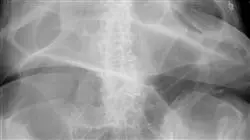

El alumno aprenderá de los mayores expertos de esta patología, a diferenciar, diagnosticar y realizar una adecuada indicación quirúrgica del rectocele, prolapso rectal, enterocele, intususcepción y úlcera rectal solitaria. Todo este material, tendrá una orientación completamente práctica, con exposición de casos cínicos, discusión de pruebas de imagen y una colección de videos ilustrativos con las mejores técnicas quirúrgicas.

El Síndrome Obstructivo Defecatorio es una patología cada vez más común en la población adulta. Se trata de una enfermedad del suelo pélvico que puede causar una gran variedad de síntomas, como estreñimiento crónico, dolor abdominal y problemas para evacuar. A través de este Curso Universitario en Síndrome Obstructivo Defecatorio, podrás dominar los últimos postulados científicos en la anatomía aplicada a esta patología, la etiopatogenia, anamnesis y la exploración física Además, tendrás la oportunidad de aprender de los mejores expertos en intervención clínica e investigación de esta apasionante área de trabajo.